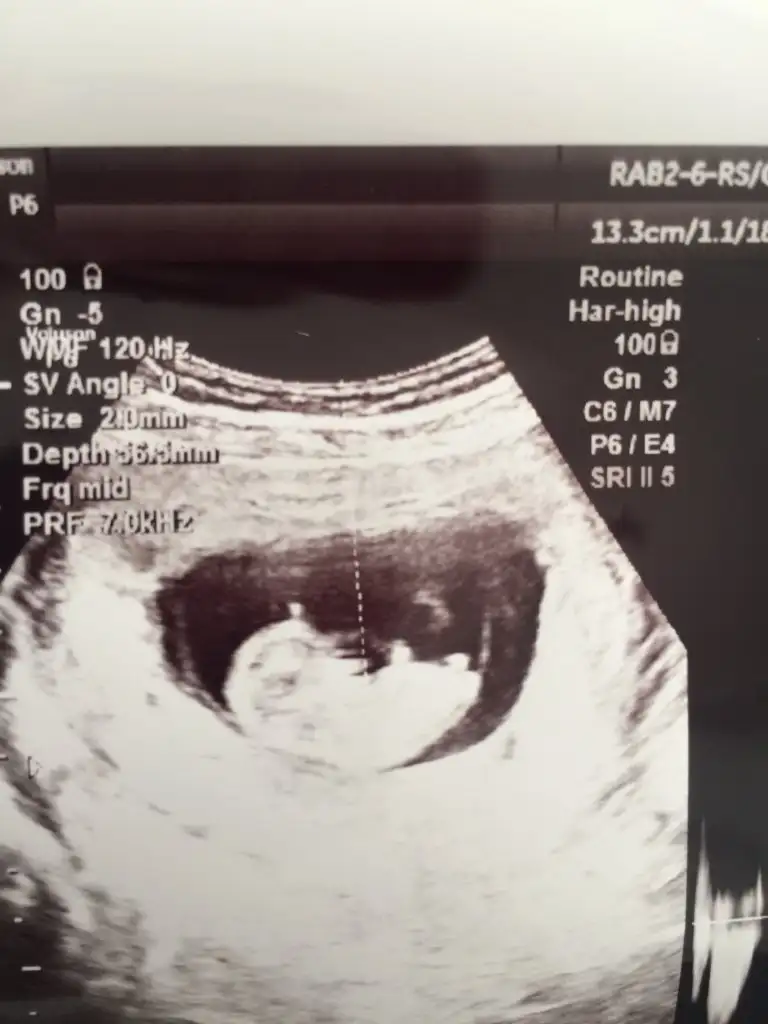

10+1 haftaya göre erkek 11 yada 12 hafta usg tekrar paylaşın çünki 10 haftalarda nub iki tarafa benzerBana da tahmin de buluabilir misiniz?daha küçük ama

Teşekkür ederim yorumladığınız için10+1 haftaya göre erkek 11 yada 12 hafta usg tekrar paylaşın çünki 10 haftalarda nub iki tarafa benzer

10+3 canımKaç haftalık

Erkek diyorum kafa yapısına göre10+3 canım